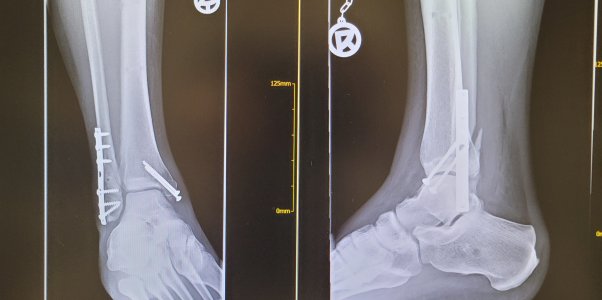

Interesse ja. Aber ich glaub ich fahr dieses Jahr nichts ambitioniertes. Verheilt nicht gut der fuss

Anhänge

• 20230209_095332.jpg

20230209_095332.jpg

1,3 MB · Aufrufe: 223

Aua! Das sieht fies aus. Ich leide aus der Ferne mit;)